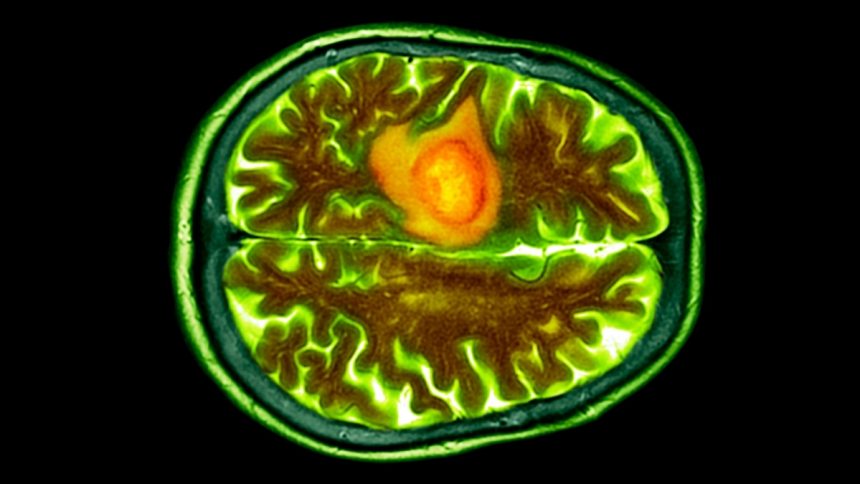

Traditionally, glioblastoma tumors have been challenging to treat due to their highly aggressive nature, late detection, and ability to evade the body’s immune response. These tumors also pose a challenge in terms of accessibility, as they often form in the brain or along the delicate central nervous system.